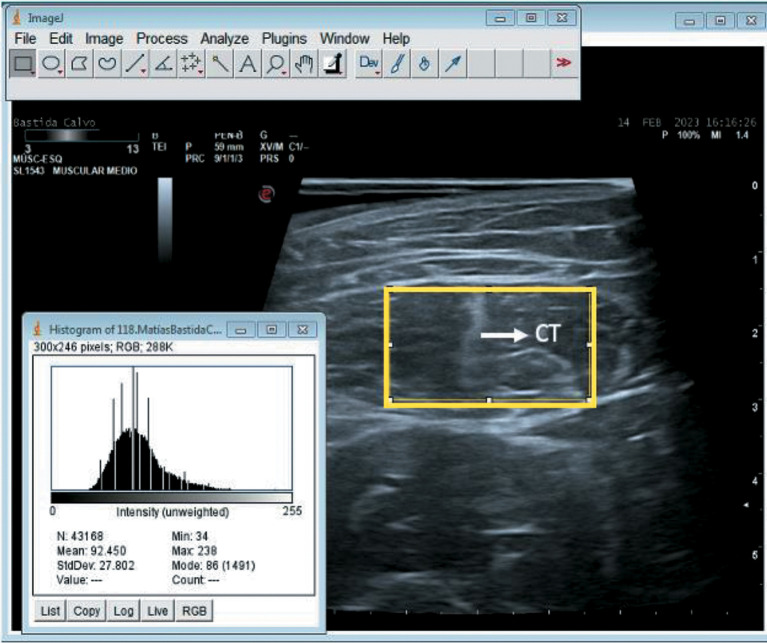

Methods: Sensitivity, specificity, likelihood ratios and area under the curve (AUC) for diagnostic efficacy of echogenicity (index test) assessed with the ImageJ software greyscale as a potential marker of quadriceps muscle weakness (reference test) were calculated. Muscle weakness was considered as maximal voluntary isometric contraction of the quadriceps (Q-MVIC) <40% of body weight. Other variables included body composition parameters derived from multifrequency electrical bioimpedance, upper limb muscle strength (handgrip), and RF thickness assessed by ultrasound. Statistical tests: Chi-square, t-Student, Pearson correlation coefficients (r), bivariate and multivariate logistic regression models. Statistical significance level ≤0.05.

Results: Of 112 patients (mean age: 63.6, 76% male), 72 (63.7%) exhibited quadriceps weakness, while 80 (70.8%) had some degree of overhydration (extracellular water/total body water ratio >0.390). The echogenicity cut-off point of highest concordance with muscle weakness was 70, boasting a sensitivity of 83%, specificity of 57%, and AUC of 0.671 (CI 95% 0.570-0.772 [P=0.003]). Echogenicity >70 was associated with a 3.4-fold higher risk of muscle weakness (crude OR = 3.4 [CI95% 1.4 to 8.0]), which persisted after adjusting for age, height, weight and RF thickness.